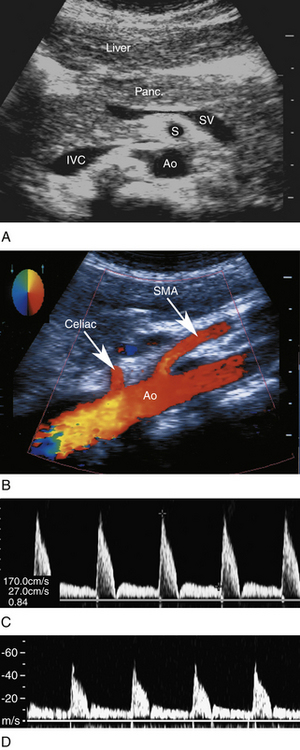

Ультразвуковое исследование чревной артерии обычно начинают с поперечного исследования проксимального отдела брюшной аорты. Поперечный доступ позволяет визуализировать разветвление печеночной и селезеночной ветвей, обычно напоминающее букву Т или «чайку» ( рис. 26-2 , А ). Продольный подход предпочтителен для оценки происхождения чревной артерии. Мы также используем продольный вид для допплеровского исследования чревной артерии. В этой проекции достигается постоянная коррекция угла, превышающая или равная 60 градусам. Этот вид также позволяет оценить СМА, которая находится чуть ниже чревной артерии.

РИСУНОК 26-2. Чревная артерия. А: Поперечная сонограмма чревной оси (С) в месте ее разделения на общую печеночную артерию (ОПА) и селезеночную артерию (СА). Ао, аорта; НПВ, нижняя полая вена; СВ — сегмент селезеночной вены. B — Нормальный допплеровский сигнал с низким сопротивлением в чревной артерии. Пиковая систолическая скорость составляет 113 см/сек, а конечная диастолическая скорость — 30 см/сек.

Характерная форма допплеровского сигнала представляет собой артериальный сигнал с низким сопротивлением ( рис. 26-2 , Б ). Как упоминалось выше, непрерывный прямой поток на протяжении всей диастолы необходим для адекватной перфузии печени и селезенки. Ветви печени и селезенки также будут демонстрировать картину низкого сопротивления.

РИСУНОК 26-7. Ультразвук верхней брыжеечной артерии (ВМА). А. Анатомические взаимоотношения СМА (S). Обратите внимание, что СМА окружена характерным слоем эхогенного жира. Поджелудочная железа (Panc.) расположена кпереди от СМА. Аорта (Ао) находится позади СМА. НПВ, нижняя полая вена; СВ, селезеночная вена. Б. Продольная проекция показывает отхождение чревной артерии и СМА от аорты (Ао). C — Нормальный высокоомный допплеровский сигнал в СМА у голодающего пациента. D. Нормальная форма волны высокого сопротивления натощак в нижней брыжеечной артерии.

Нижняя брыжеечная артерия (НБА) отходит от брюшной аорты ниже почечных артерий, выше бифуркации подвздошной кости. Он начинается в левой переднебоковой части аорты и идет вниз и влево. НМА обеспечивает кровоснабжение дистального отдела толстой кишки и проксимального отдела прямой кишки. Между СМА и НБА имеется несколько коллатеральных контуров, включая дугу Риолана и маргинальную артерию Драммонда.

Кровоток при СМА и НМА лучше всего оценивать с помощью продольных ультразвуковых изображений, поскольку длинный сегмент сосуда визуализируется с одной точки зрения. Допплеровские волны обычно получаются на этом продольном снимке на уровне начала и проксимальных сегментов.

Допплеровские волны SMA и IMA демонстрируют умеренную турбулентность вблизи артериального начала; однако при движении дистально поток становится более равномерным. У голодающего пациента в СМА и НМА наблюдается картина потока с высоким сопротивлением (см. рис. 26-7 , C и D ) с резкими систолическими пиками и небольшим диастолическим потоком. Однако в течение 30–90 минут после еды формы волн SMA и IMA могут принять характер низкого сопротивления, с широкими систолическими пиками и непрерывным диастолическим потоком.